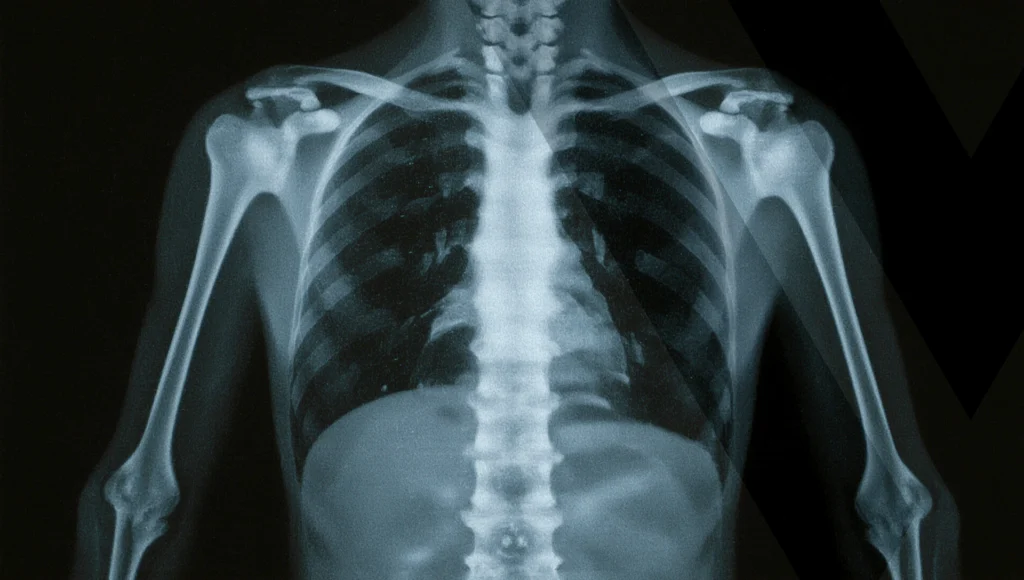

Die Orthopädie befasst sich mit der Erkennung, Behandlung und Vorbeugung von Beschwerden des Bewegungsapparates – also von Gelenken, Muskeln, Sehnen, Bändern und Knochen.

Unser Fokus liegt auf konservativen Behandlungsmethoden, die individuell auf Ihre Bedürfnisse abgestimmt werden. Dazu gehören unter anderem präzise Diagnostik, moderne Therapieverfahren und persönliche Betreuung.

Ob Rückenschmerzen, Gelenkbeschwerden oder Überlastungssymptome – wir unterstützen Sie mit fachlicher Kompetenz und ganzheitlichem Blick auf Ihre Gesundheit.